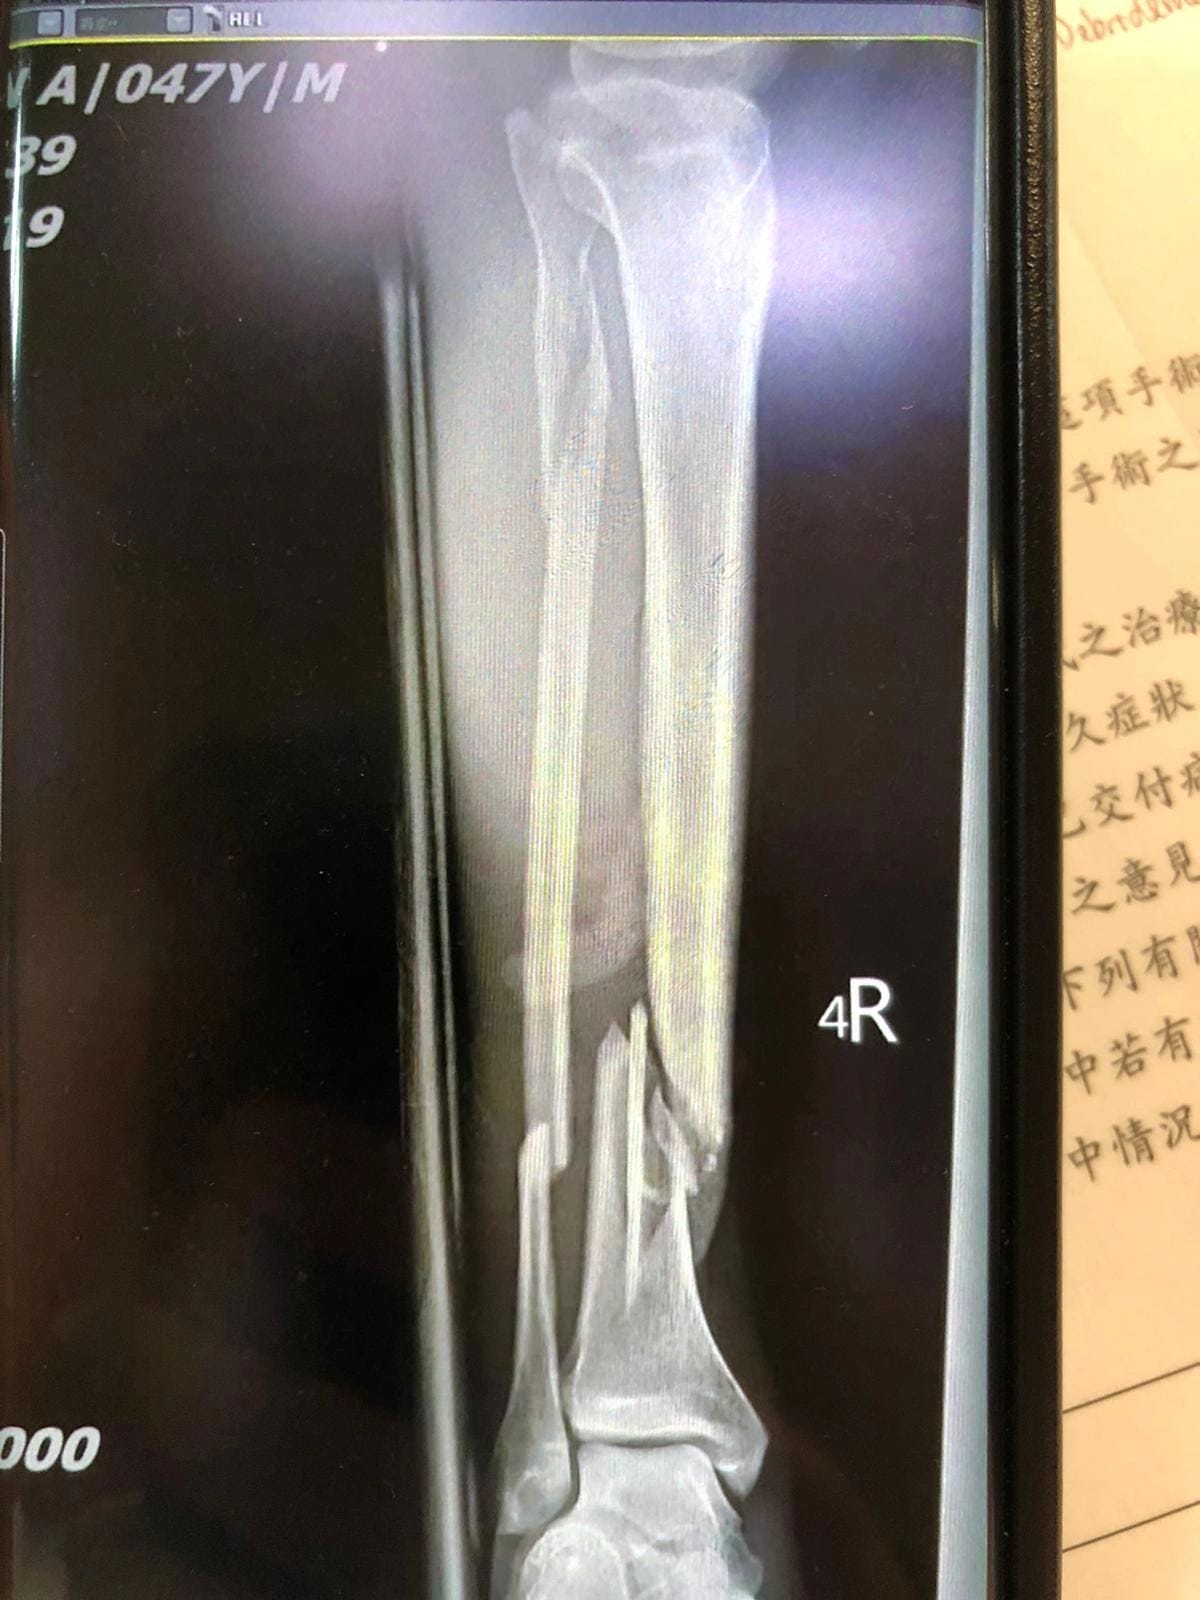

I have so many healed broken bones, I’ve lost track. When asked on medical forms how many broken bones I’ve had, I have to give a range. At various times, I’ve broken ribs, fingers, both thumbs, my hand, my left arm, my right leg, vertebrae (vertebrae?! Holy crap!)... I broke my arm mountain biking and my leg in a scooter accident. When I say broke, I mean in each case I mean that bones were in splinters with pieces sticking out of the skin.